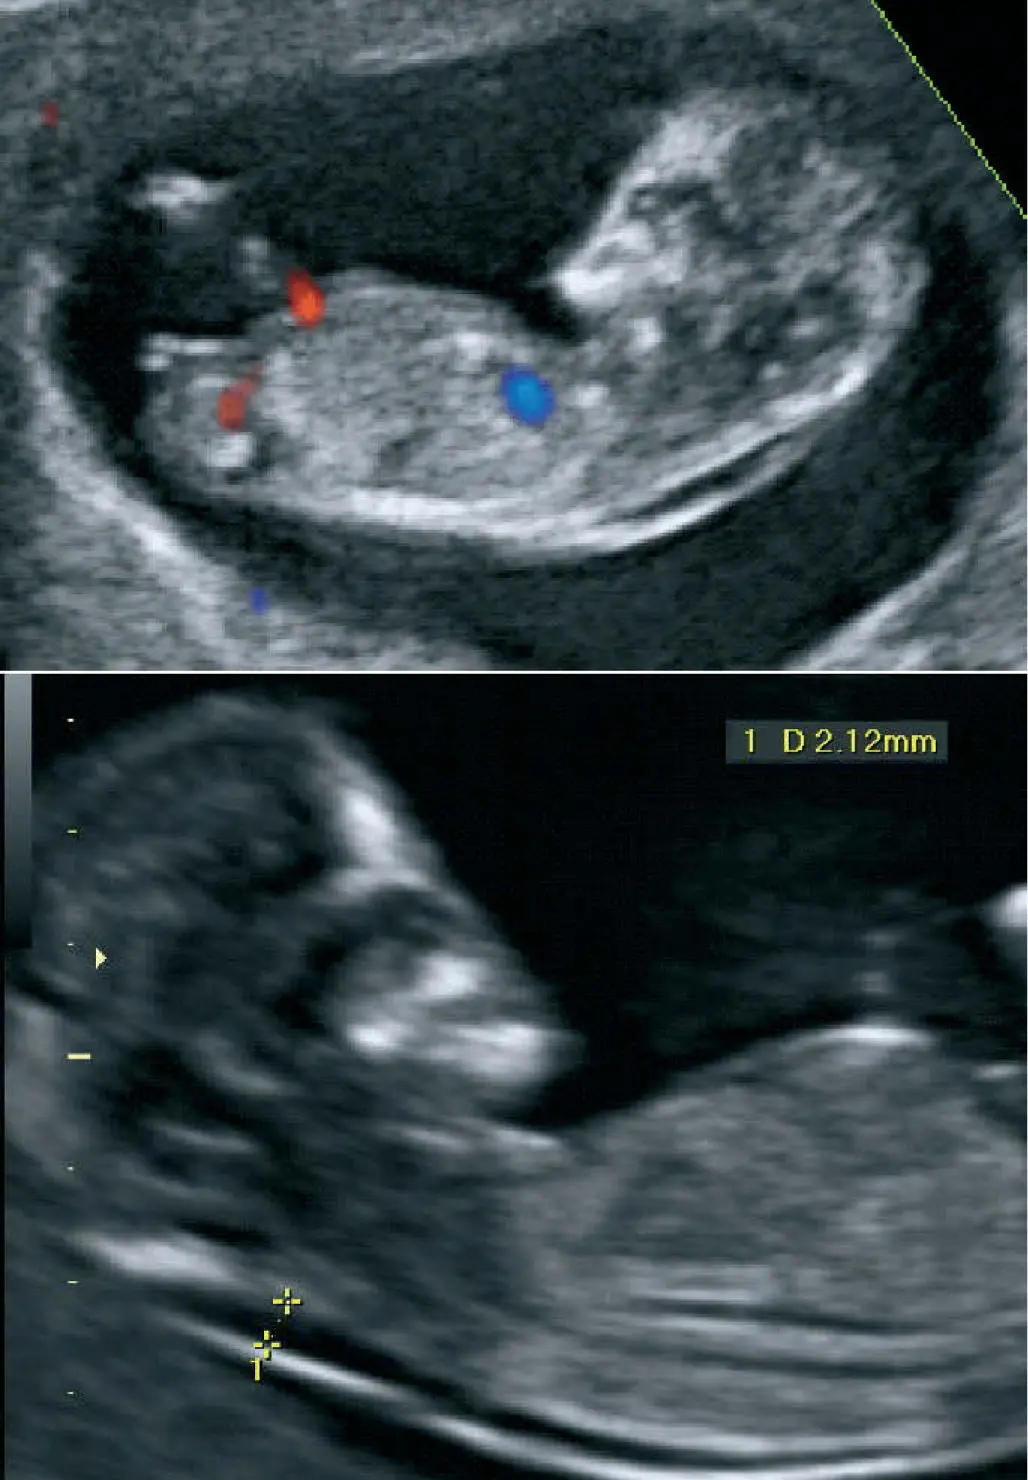

Doppler Obstétrico: Esta técnica adicional mide el flujo sanguíneo en las arterias del feto y la placenta, proporcionando información sobre el bienestar fetal y el riesgo de preeclampsia.

- Examinar los patrones de flujo sanguíneo.

La ecografía obstétrica permite visualizar diversas estructuras fetales y maternas. En el primer trimestre, se pueden observar el saco gestacional, el embrión, el latido cardíaco fetal, y la translucencia nucal. En trimestres posteriores, se evalúa la anatomía fetal completa (corazón, cerebro, órganos abdominales, etc.), la cantidad de líquido amniótico, la placenta y el crecimiento fetal.